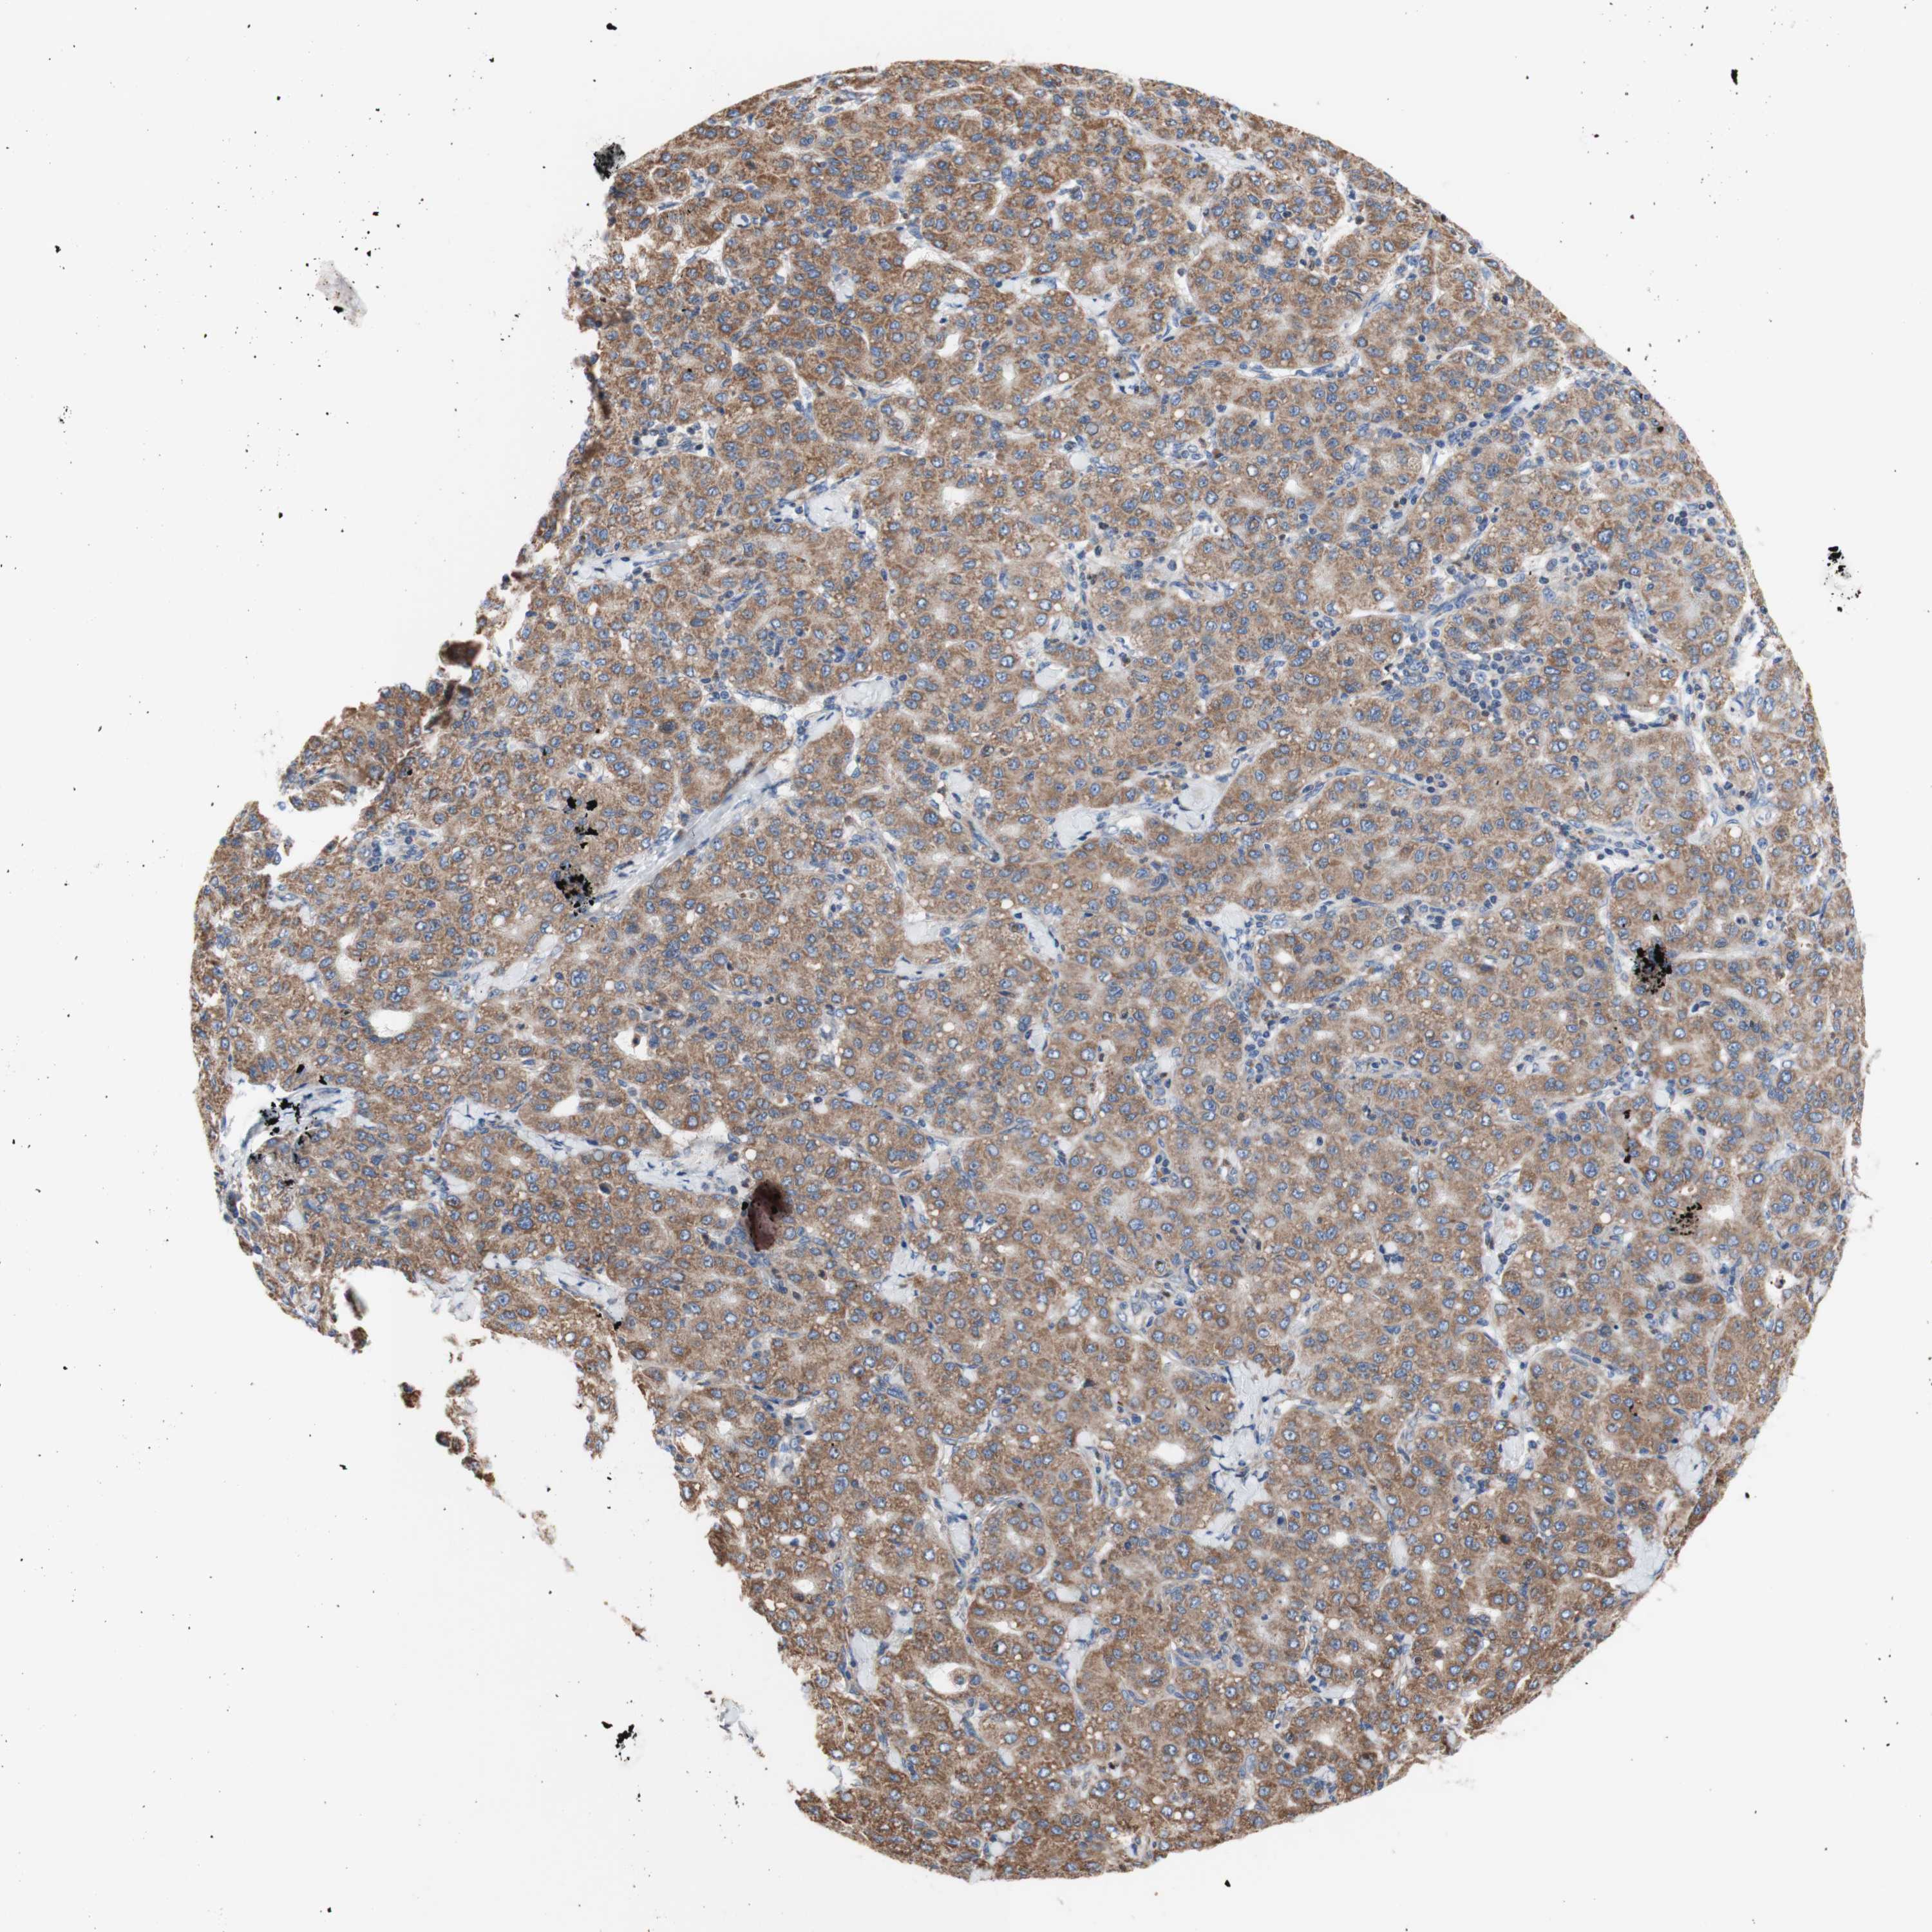

LIVER CANCER - Protein expressioni

A mouse-over function shows sample information and annotation data. Click on an image to view it in a full screen mode. Samples can be filtered based on level of antibody staining by selecting one or several of the following categories: high, medium, low and not detected. The assay and annotation is described here.

Note that samples used for immunohistochemistry by the Human Protein Atlas do not correspond to samples in the TCGA dataset.

Antibody stainingi

Antibody staining in the annotated cell types in the current human tissue is reported as not detected, low, medium, or high, based on conventional immunohistochemistry profiling in selected tissues. This score is based on the combination of the staining intensity and fraction of stained cells.

Each image is clickable and will lead to virtual microscopy that enables deeper exploration of all samples and also displays staining intensity scores, fraction scores and subcellular localization as well as patient and tissue information for each sample.

Antibody HPA050118

Antibody HPA056084

Antibody CAB012444

Staining

High

Medium

Low

Not detected

Intensity

Strong

Moderate

Weak

Negative

Quantity

>75%

75%-25%

<25%

None

Location

Nuclear

Cytoplasmic/membranous

Cytoplasmic/membranous,nuclear

Carcinoma, Hepatocellular, NOS

Cholangiocarcinoma